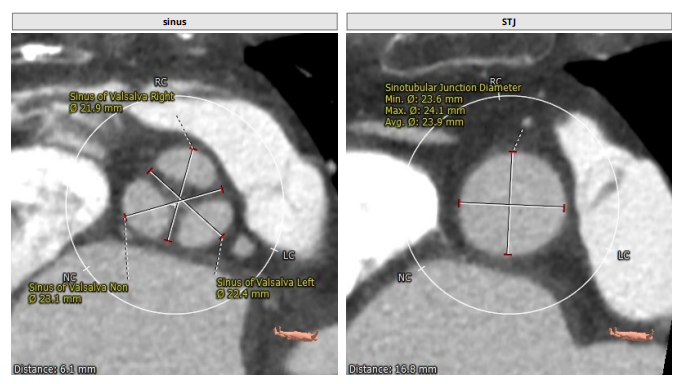

术前CT评估

整体情况

瓣环:16.9mm;左室流出道:16.7mm

STJ:23.9mm;升主动脉:31.4mm

瓣叶增厚 右冠高度:10.9mm

左冠高度:9.5mm

工作体位:LAO:12°CRA:5° ;左冠切线位:LAO:26° CRA:19°

患者为三叶瓣,左右、右无疑似粘连,瓣叶明显增厚,轻度钙化。右冠高度10.9mm,左冠高度9.5mm,冠脉高度均较低。法式窦小,心脏角度不大,左室大小可,升主动脉未见明显增宽,病人整体结构小,瓣环仅有16.9mm,左室流出道16.7mm,窦管结合部23.9mm,升主动脉31.4mm。选择右股作为主入路。